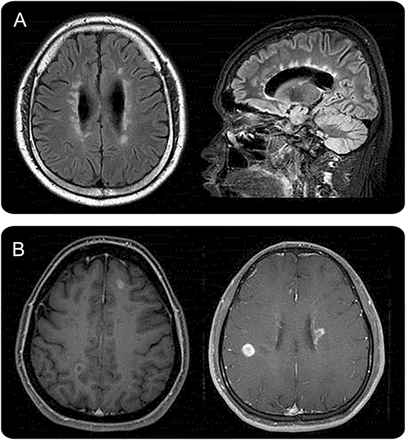

动的最明显的表现是LETM,定义为损伤时间跨度超过3或更多相邻椎段和主要涉及中央灰质在脊髓磁共振成像(图4)。4然而,并不是所有LETM LETM患者NMOSD,几项研究已经观察到显著的人口和临床特征差异anti-AQP4 LETM患者抗体正面与负面。19,36,- - - - - -,38LETM似乎不太特定的动的儿童比成年人。LETM经常被观察到在儿童急性播散性脑脊髓炎39,40也有17%的女士,e25在67%到88%的儿童单相横向脊髓炎。e26, e27因此,重要的是要记住,许多其他比NMOSD鉴别诊断时需要考虑病人与LETM礼物。